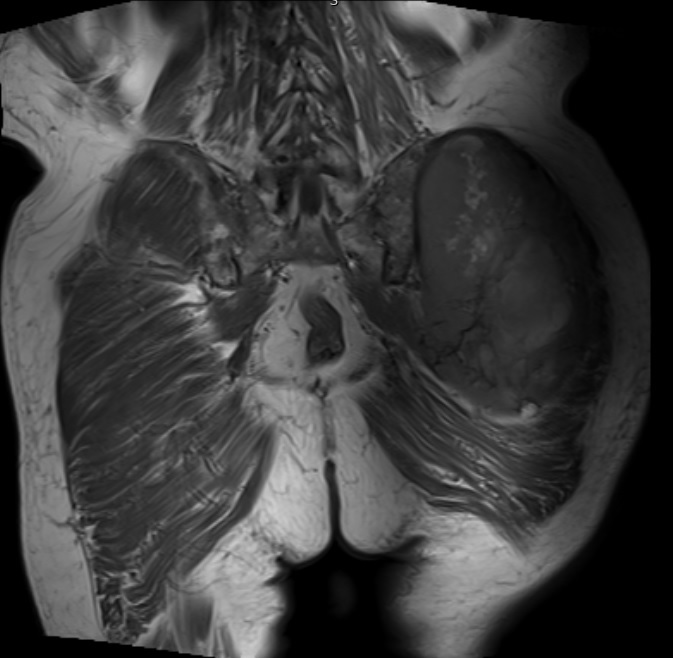

Fig. 1 & 2 Magnetic Resonance Image shows a large heterogeneous mass in the left gluteal region with low intensity signal on Axial (Fig. 1) and Coronal (Fig. 2) T1-weighted images admixed with some high signal areas indicative of fatty tissue. Higher intensity signal is visible compatible with hemorrhage or necrotic tissue. The mass involve the central portion of the left iliac bone.

Fig. 3 Axial fat suppressed T2-weighted MR image demonstrates a large heterogeneous mass with multiple thick internal trabeculations. Fatty areas suppress on T2 weighted fat suppressed areas